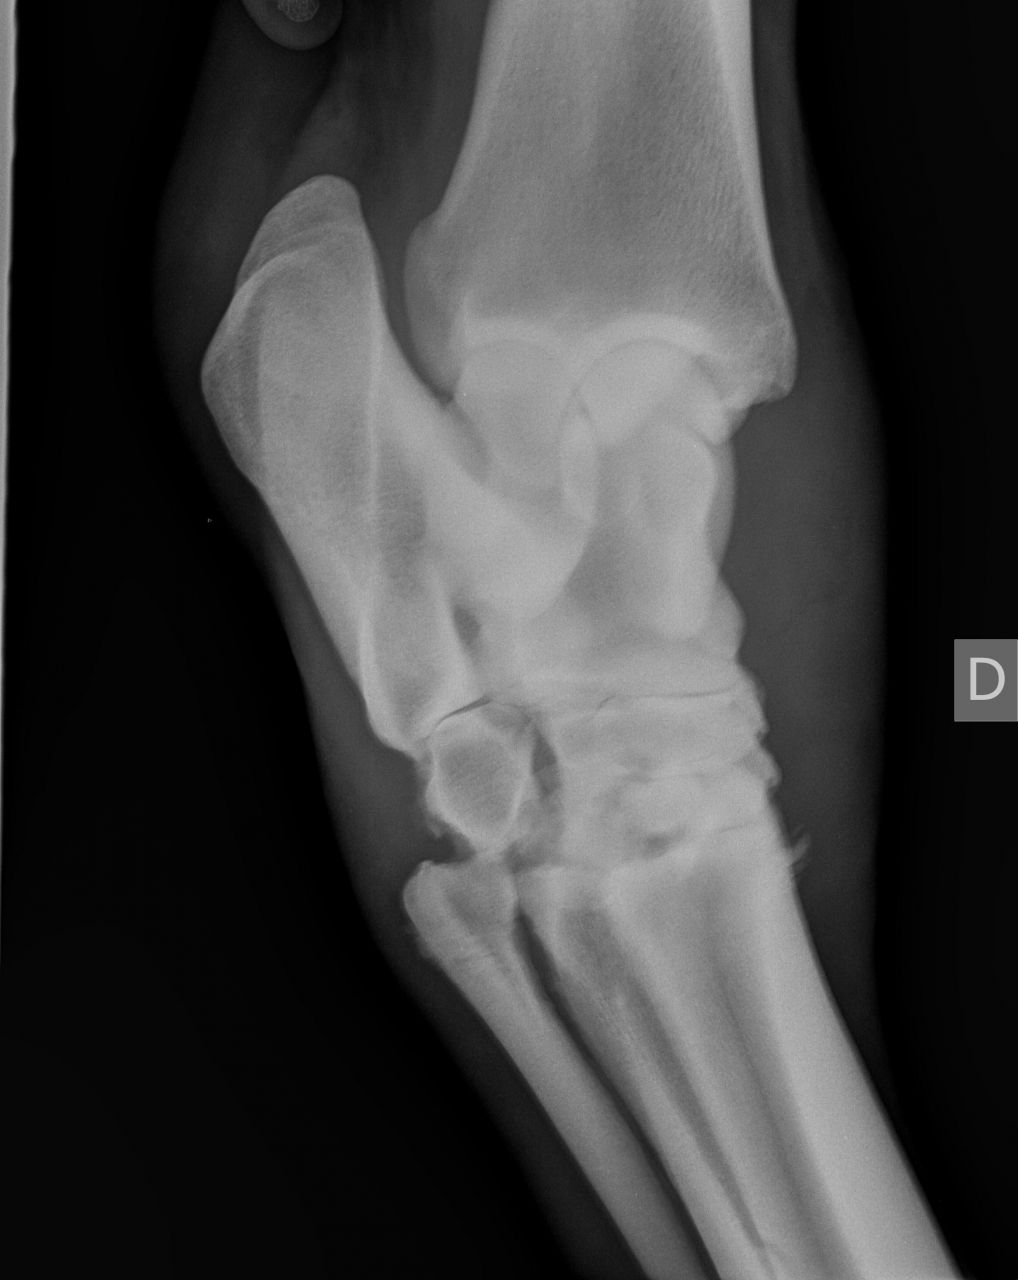

| Dire merci | Voici une radio prise en octobre 2010, [url=https://www.1cheval.com/membre/services/photos/images/191702.jpg" class='zoombox zgallery3279789' ] ![]() et une en décembre : [url=https://www.1cheval.com/membre/services/photos/images/191703.jpg" class='zoombox zgallery3279789' ] ![]() comme tu vois, c'était pas joli joli ! |

| Dire merci | je ne sais pas comment on fait pour entourer. Mais si on regarde tout les pourtours de ses articulations du jarret ne sont pas nets, il y a de l'arthrose et des détachements osseux. En faite, ca s'est décalcifié de partout et ca s'est recalcifié comme ca a pu et ca a fait une arthrodèse du jarrêt (sur le second cliché, on ne distingue plus vraiment les os, ca fait des blocs) |

| Dire merci | Voici 2 autres clichés encore plus parlant : en octobre : [url=https://www.1cheval.com/membre/services/photos/images/191705.jpg" class='zoombox zgallery3279806' ] ![]() en décembre : [url=https://www.1cheval.com/membre/services/photos/images/191706.jpg" class='zoombox zgallery3279806' ] ![]() oh, tu sais, aujourd'hui, j'en parle s'en soucis et en étant contente du résultat, mais au moment où, je suis passé par des questionnements et des remises en cause pas possible, est ce que je fais bien, est ce que j'ai raison, ne devrais-je pas écouter les autres et ne pas m'acharner, etc...? sauf que les autres, ils ne sont pas à ta place, alors, j'ai écouté mon instinct. financièrement, j'y ai laissé des plumes, heureusement, les dépenses étaient étalées car dur avec un smic. Et pis, ben une fois qu'on a commencé, on va jusqu'au bout, pas possible à mi-parcourt d'arrêter, vaut mieux alors ne pas commencer. Je comprends par quoi tu passes. La fêlure de ton cheval n'est pas si grave que ca. Evidemment, c'est un mot impressionnant, surtout qu'on associe facilement chez le cheval fracture= fichu. Qu'est il envisagé comme soins pour ton cheval? Qui est-il? A quoi est-il destiné? |

| Dire merci | Chez ma jument, ce n'est pas une fracture au sens on on l'entend, c'est à dire une cassure de l'os. C'est plus une facture au sens large du terme, où on prend en compte la globalité de l'articulation. On voit qu'il y a pleins de petits éclats, qu'il n'y a plus d'espace entre les os et qu'ils se soudent entre eux. Désolée, je ne suis pas véto, j'explique avec mes mots, je ne suis pas précise. |